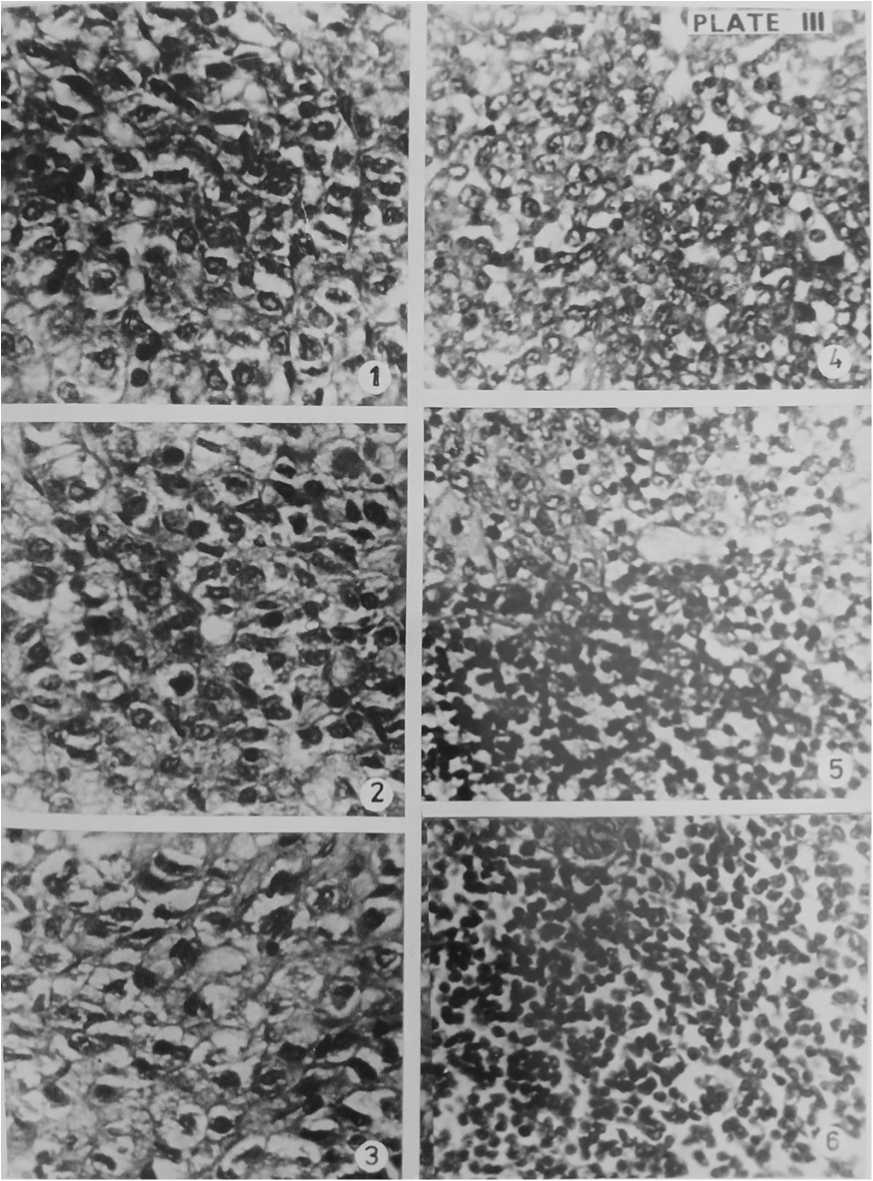

Figure 3. Section of Pituitary gland (1), Thyroid gland (2), Adrenal gland (3), Pancreas (4), Liver (5), Testis (6), Kidney (7) and Muscle tissue (8) of Experimental Gerbil after 1st dose of BHC + Food treatment. Haematoxylin- Eosin × 400

Figure 4. Section of Pituitary gland of Normal Gerbil (1), Control Gerbil (2), Experimental Gerbil after 14 days of BHC + Food treatment (3) & Section of Thyroid gland of Normal Gerbil (4), Control Gerbil (5), Experimental Gerbil after 14 days of BHC + Food treatment (6). Haematoxylin- Eosin × 400

Figure 5. Section of Adrenal gland of Normal Gerbil (1), Control Gerbil (2), Experimental Gerbil after 14 days of BHC + Food treatment (3) & Section of Pancreas of Normal Gerbil (4), Control Gerbil (5), Experimental Gerbil after 14 days of BHC + Food treatment (6). Haematoxylin- Eosin × 400

The pitutory gland is composed of three lobes: anterior, intermediate and posterior. The anterior lobe is a dorsal evagination called the adenohypophysis and posterior to be derived from central infundibular evagination called neurohypophysis. There is an intermediate enlargement of posterior part of adenohypophysis called intermediate lobe. (Figure 4). Normal and control Gerbils did not show notable histopathological changes in pituitary glands. The pituitary gland of BHC treated animals showed remarkable changes on the 7th day. The cells of these glands became constricted. The cells of the peripheral part separated from each other. The adenohypophyseal and neurohypophyseal parts of pituitary gland deformed. On 14 days of treatment there developed vacuoles inside the cells. There appeared binucleate stage due to the breakage of adjacent cells. Constriction and shrinkage of cells made spaces and clefts in the various parts of the gland. Certain cells broken into bits. Aggregations of haematoxylin and eosin staining granules were present here and there. It is clear that the pesticide BHC caused damage to the pituitary gland. (Figure 3 and 5).

Thyroid gland is a bilobed gland lying on the central side of the trachea. The gland is composed of varying numbers of irregularly rounded thyroid follicles of different sizes. The follicles are closely packed together and each is surrounded by a basement membrane. The epithelial cells may be flattened or tall and columnar. (Figure 4). The normal and control antelope rats showed normal nature of the gland. The thyroid glands of BHC treated animals were damaged. Cells constricted and separated on the 7th day analysis. Due to the formation of vacuoles inside the thyroid follicles the section of the 14 day treated BHC fed animals appeared in the form of a loose net. Cleft formations were many when compared to pituitary gland on the 14th day analysis. Separated cells and splitted cells were found due to decaying of thyroid gland. (Figure 3 and 5).

The adrenal glands lie at the anterior end of the kidneys. They are a pair of compact bodies and each with two distinct regions, inner medulla of ectodermal origin and outer cortex of mesodermal origin. The medulla contains fine cytoplasmic granules called chromaffin granules. The adrenal cortex is found to consist of an outer zona glomerulosa layer, middle zona fasciculata layer and an inner zona reticularis . The cells of the medulla are more homogeneous in appearance than those of cortex. The cells of the medulla are irregularly arranged and secretory in nature. (Figure 5).

The adrenal glands of experimental gerbils only showed histopathological changes. On the seventh day of BHC treatment, the cortex was damaged, clumps of nuclei and space formation observed. In medulla region also shrinkage of cells, damaged chromaffin cells and space formation were noted. The experimental gerbils that consumed the 2nd dose of BHC on the 14th day, zona fasciculata of the cortex were ruptured and their nuclei were pycnotic and vacuolations developed. Some of the cells of this region were binucleated and space formation noticed. In medulla region due to shrinkage of cells spaces formed and ruptured chromaffin cells in compact mass. Chromaffin cells were hypertrophied and their nuclei were pycnotic. Due to splitting big venules were formed in medulla. BHC damaged the adrenal gland of gerbil. (Figure 3 and 5).

Pancreas is provided with two distinct kinds of tissues, the exocrine and endocrine tissues. In the exocrine portion, the secretory cells making up the alveoli and among the alveoli there lies masses of epithelial cells which are in variable size, the islets of Langerhans, the endocrine tissues. (Figure 4). On examination, the histology of the pancreas of normal, control and experimental antelope rats found to be normal after consuming completely the first and 2nd doses of food i.e. after the 7th day as well as after the 14th day. The cells of the alveolar tissue as well as the islets of Langerhans were not disturbed. It was noticed that the pesticide BHC had only very little toxicity effect in the pancreas of gerbil. (Figure 3 and 5).